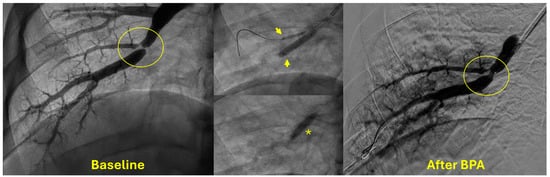

4. Indications and Patient Selection for BPA